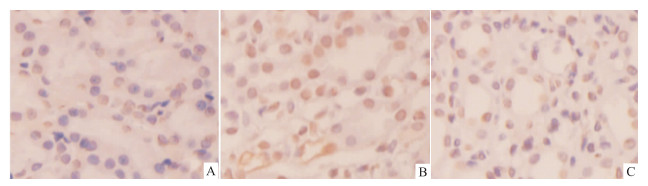

SP法免疫组化检测结果显示,Bax和caspase-9蛋白主要表达在肾小管上皮细胞(Fig5)。由Tab2可知,顺铂模型组的Bax、caspase-9表达水平均明显高于空白对照组(P<0.01),分别升高5.38、1.75倍;与顺铂模型组比较,顺铂+PNS组的Bax和caspase-9表达水平均明显降低(P<0.01),分别下降50.9%和30.2%。

|

| Fig 5 Expression of Bax and caspase-9 detected by immunohistochemistry A-C:Bax expression,D-F:caspase-9 expression. A,D:Control;B,E:Cisplatin;C,F:Cisplatin+PNS. |